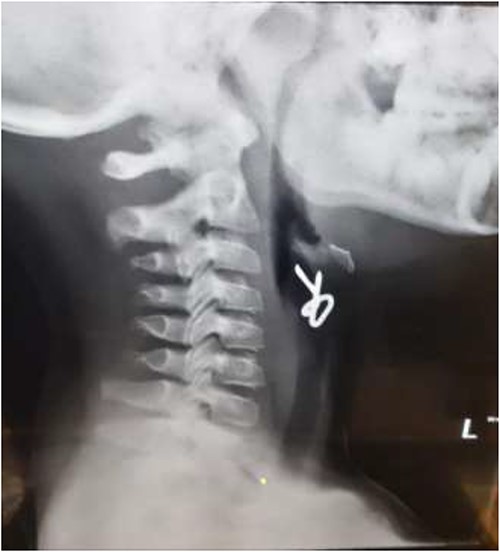

The second case involved a 3-year-old child who presented with sudden onset noisy breathing. Inspiratory stridor was evident on examination. Radiographs of the neck again showed a radio-opaque object in the upper airway (Fig. 4). Apnoeic oxygenation allowed for tubeless anaesthetic and safe removal of the metallic foreign body from the airway (Fig. 5).

Lateral neck X-ray showing a radio-opaque object in the upper airway.